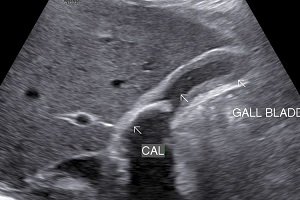

• Cholelithiasis: Presence of calculus/ calculi in gall bladder with normal wall thickness is known as cholelithiasis.

• Findings: Shows presence of calculi in gall bladder/ common bile duct, its mobility & complications.

• Solitary Calculi: